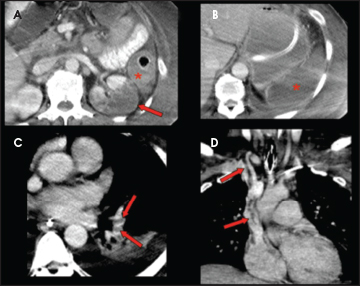

- Risque plus rare de Thromboses comme complication → HITT

- Thromboses artérielles ou veineuses

- Suspicion+++ si présence de Thromboses Artéreilles ET veineuses simulatnées